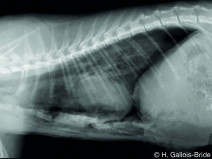

• Mise à jour des connaissances en imagerie médicale

La radiographie reste l’examen de première intention pour évaluer le thorax. Cet examen est facile à réaliser, peu couteux, et apporte de nombreuses informations si les bases anatomiques, sémiologiques et d’interprétation sont connues.

L’AFVAC section Antilles-Guyane vous propose dans ce sens une formation sur la radiographie du thorax.  Cette formation aura pour but de reprendre des él...

• Après- midi Travaux pratiques de radiographie / TP2 Le Thorax

Le GEIM vous propose une séance de travaux pratiques de radiographies sur le thorax. Tous les aspects sont abordés sous la forme de TP de lecture de radiographies numériques sur station de travail Osirix sur Mac (3 vétérinaires maximum/ordinateur).